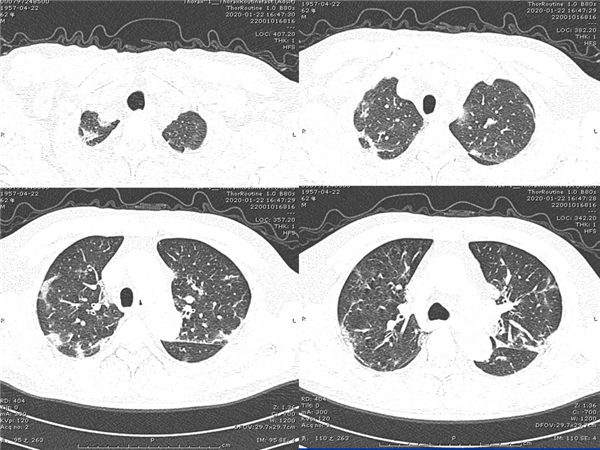

【病例分享】新型冠狀病毒感染肺部CT影像4例(常德市第一人民醫(yī)院)